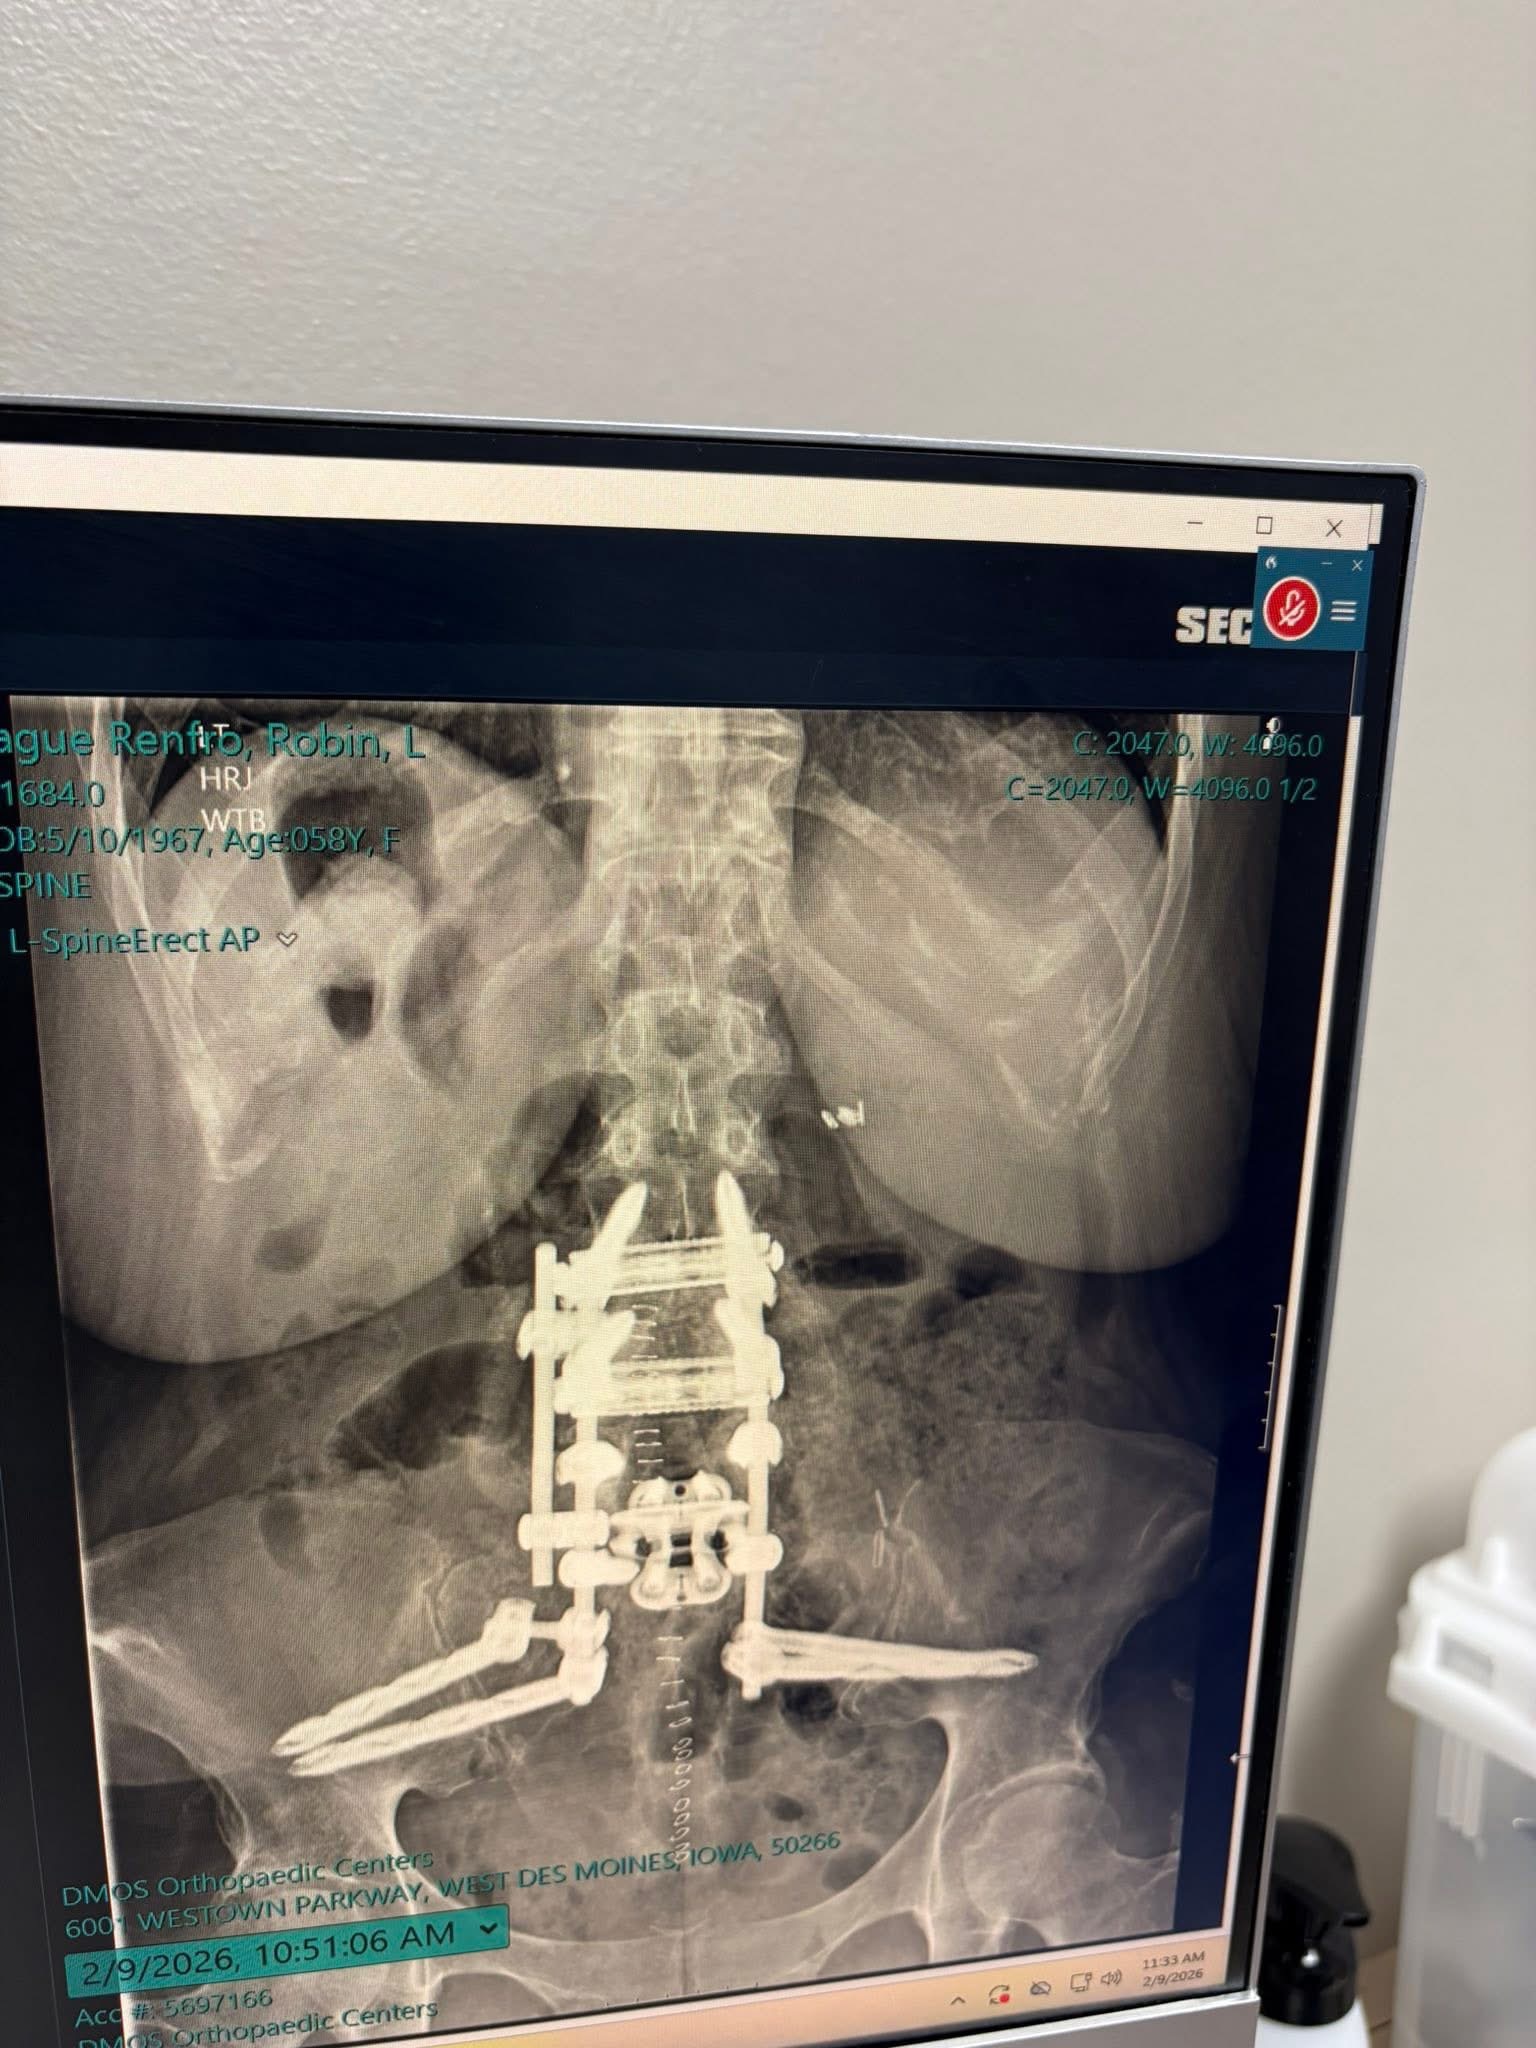

Robin recently underwent a major reconstructive back surgery due to severe degenerative disc disease, making it her eighth spinal surgery. During this procedure, all of the existing hardware in her spine had to be removed and replaced. What was already a complex and risky surgery quickly turned into a long and difficult fight for her life.

Since the operation, Robin has faced serious complications, including multiple blood transfusions, two weeks-long hospital stays, and sepsis. She has endured two additional surgeries to drain sepsis infections in her back and is now facing a lifelong course of antibiotics. Her immune system is severely weakened, and her recovery has been far more challenging than anyone expected.